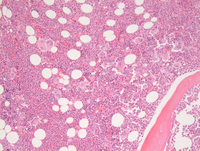

Bone core biopsy

The bone marrow biopsy specimen shows a hypercellular bone marrow (80-85%).  Although the cellularity is due somewhat to panmyelosis, the predominant cells are megakaryocytes and granulocytes. Megakaryocytes are prominently increased in number.

Bone core biopsy higher power

The megakaryocytes are of variable size, ranging from normal to enlarged forms with somewhat hyperlobulated nuclei. A few smaller forms are also seen. None are bizarre,however, and they generally lack the "bulky" nuclei observed in primary myelofibrosis.

Granulopoiesis is shifted towards segmented neutrophils, which are focally very abundant.  Erythropoiesis is primarily limited to small scattered islands and is overall at least relatively reduced in quantity. There is some shift towards pronormoblasts, but maturation is seen as well. Although blasts are observed scattered throughout the biopsy, they appear only minimally increased in percentage.

The bone trabeculae show some variability, ranging from somewhat thinned to thickened bone. There is a definite increase in reticulin fibers, 1-2+/3+ noted on the reticulin stain.

A CD34 stain showed 5% blasts.